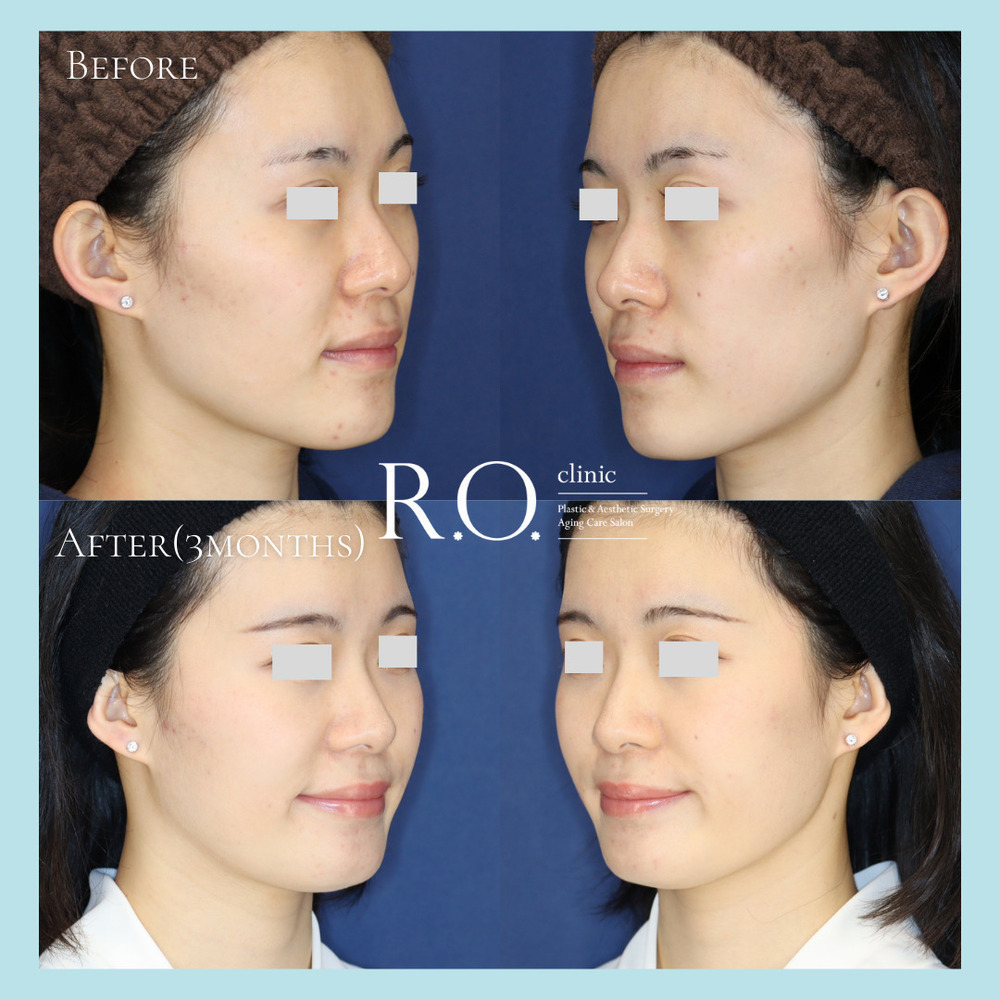

《 注目の症例 》

施術名】頬骨骨切り+あごオトガイ骨切り(中抜き)

【費用】通常価格 2,310,000円

【リスク・副作用】腫れ、内出血、左右差、口の開けにくさ、頬・下あごの知覚障害など

【施術名】下あごオトガイ骨切り(中抜き)

【費用】通常価格 1,100,000円

【リスク・副作用】腫れ、内出血、左右差、あご下のたるみ、下あごの知覚障害など